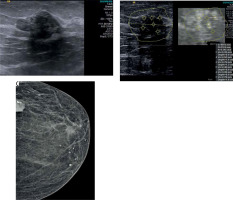

Figure 3

A) A 77-year-old old woman; irregular lobulated contoured, hypoechoic, solid, mucinous cancer on B-mode ultrasonography image. B) Virtual Touch Quantification (VTQ) measures a mean shear wave velocity (SWV): 4.1 m/s in the lesion. C) Deep localised, lobulated contoured, dense, mucinous carcinoma containing calcifications in the left quadrant of the left breast on craniocaudal mammography